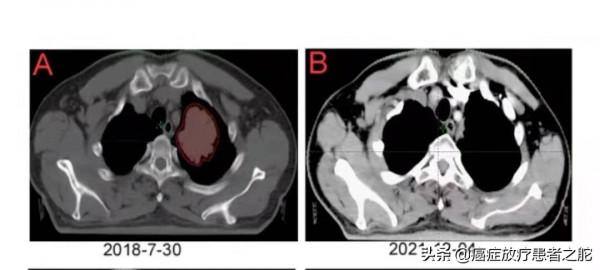

近期患者到醫院複查,肺內轉移病灶,放療後徹底消失。而且,去年上半年,肝臟復發區域,也進行了放療干預,這次複查,提示效果也很不錯。具體如下圖所示: